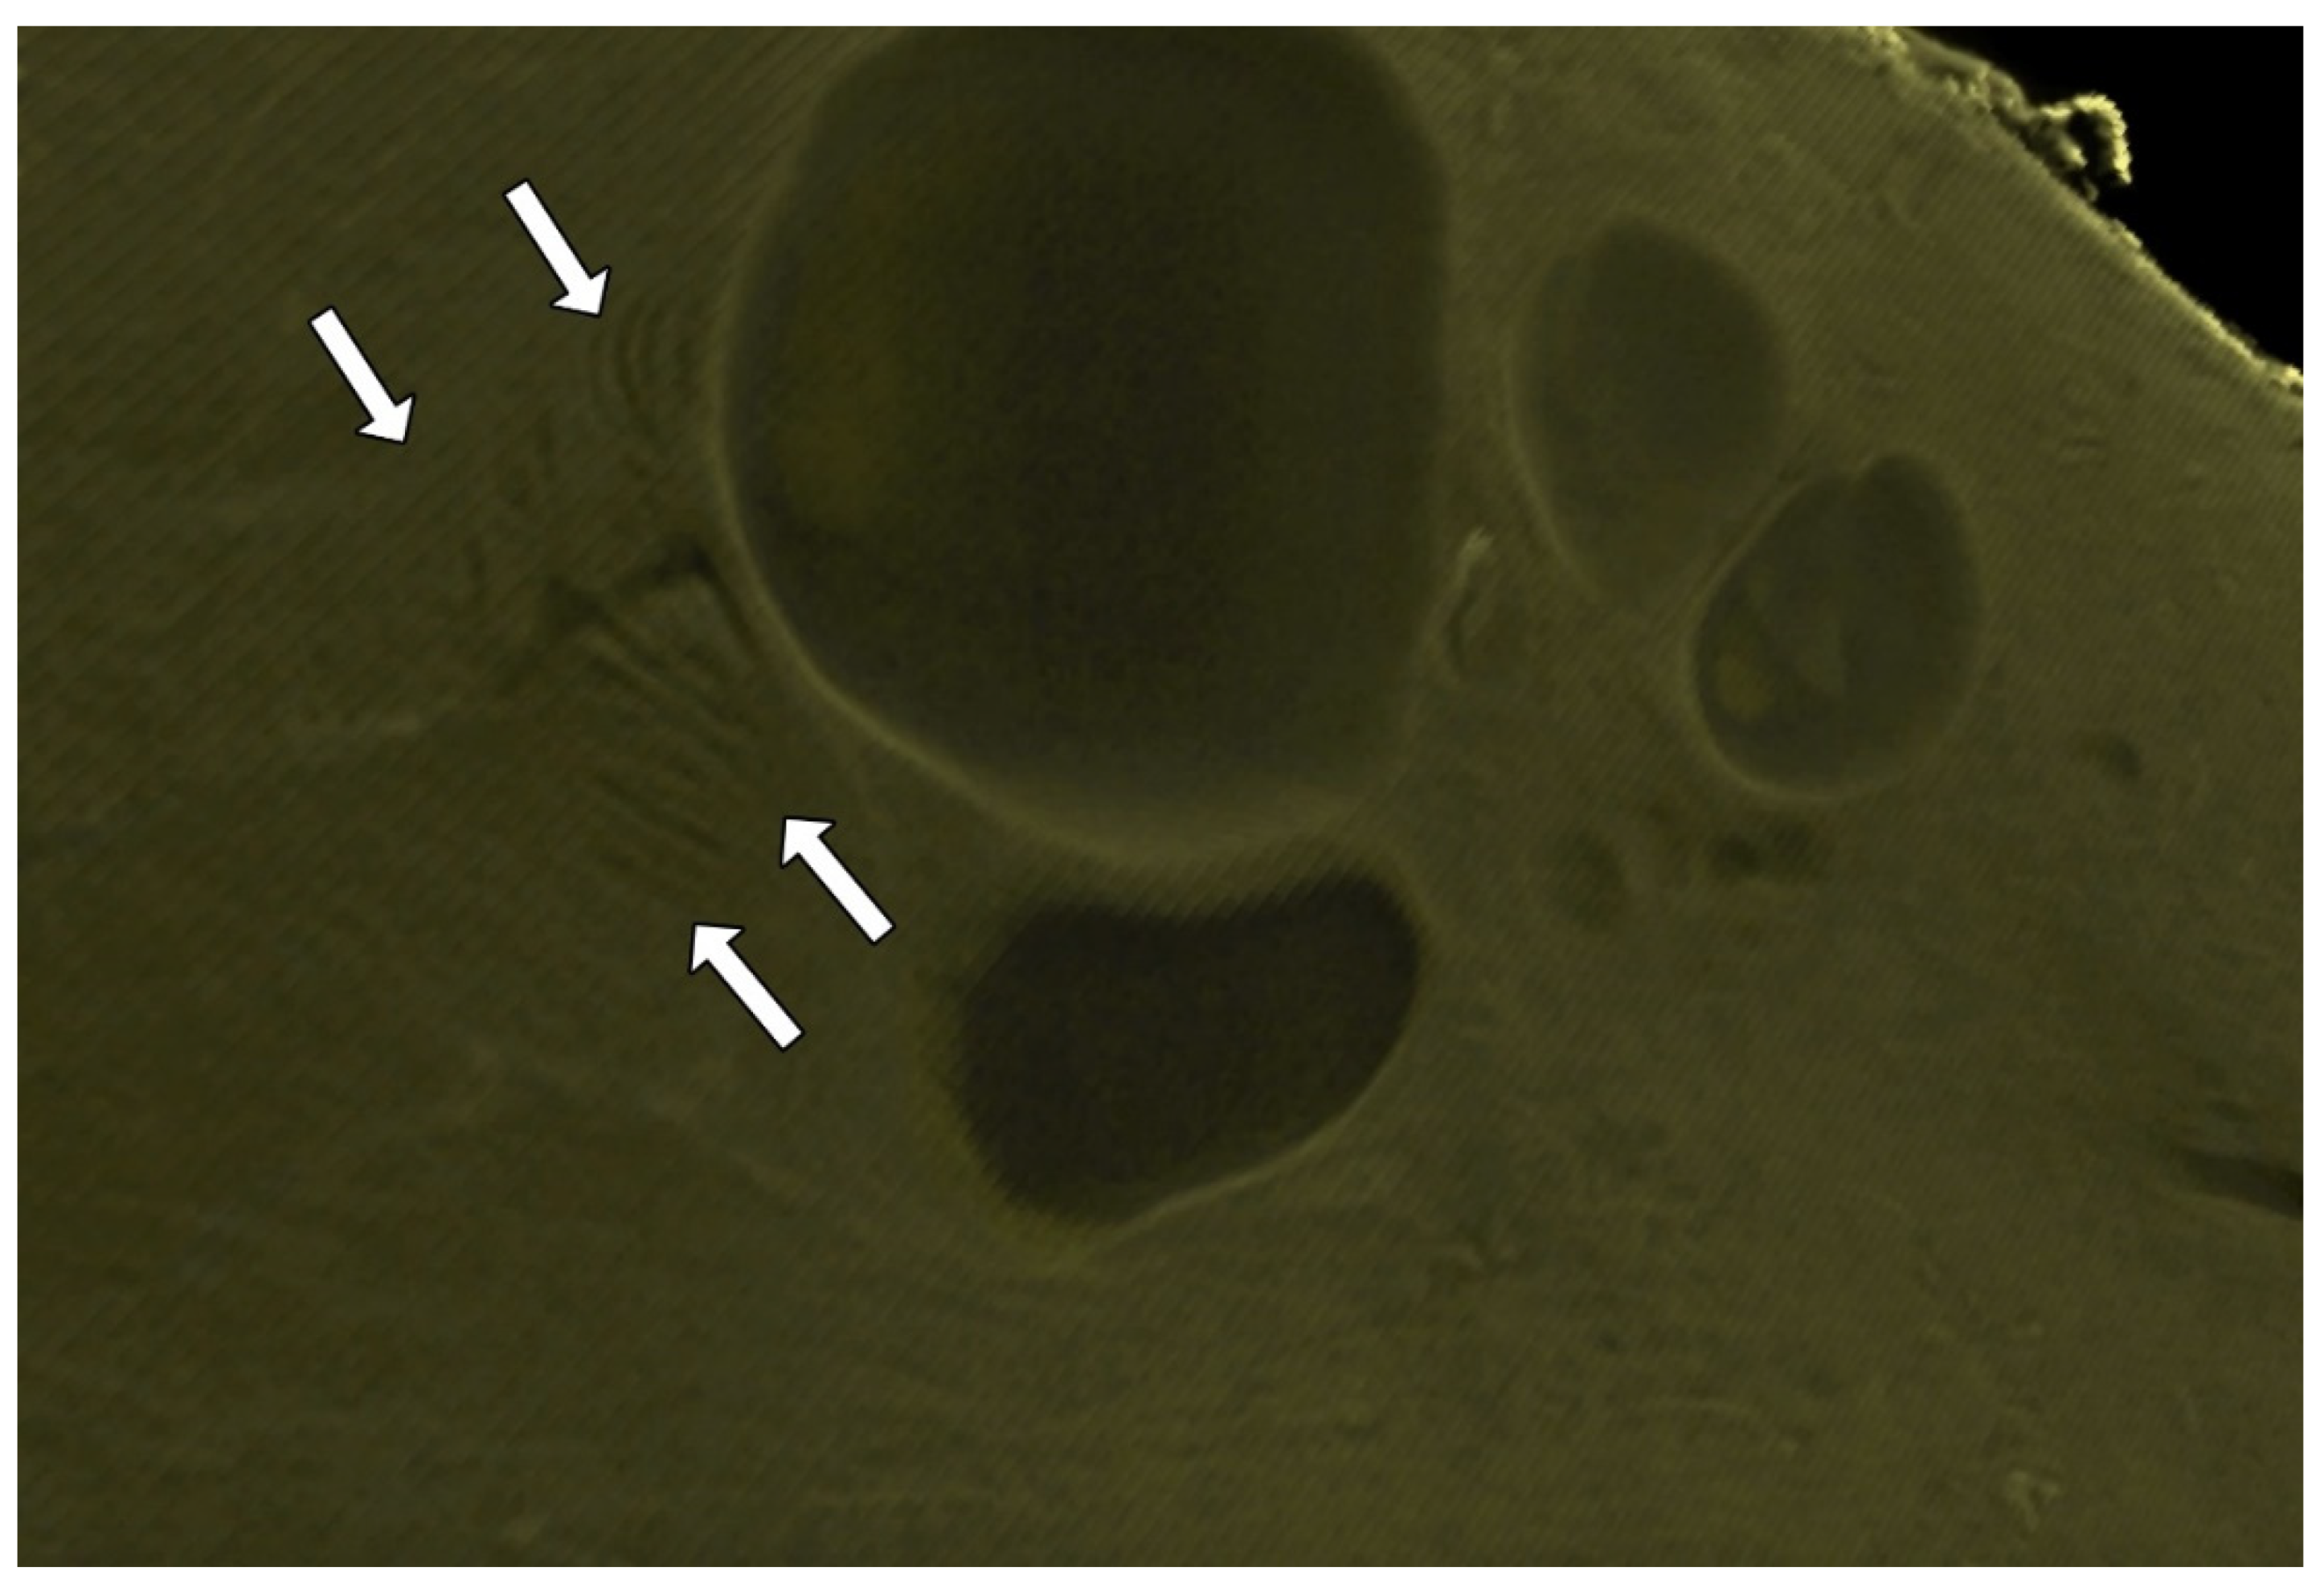

3.6. The Endocervical Canal Beyond the External os

4. Discussion